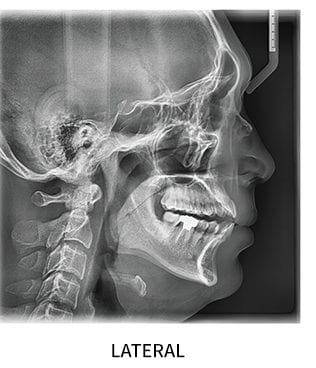

CEFALOSTATO

Il macchinario in dotazione al Centro consente, grazie a un moderno sistema digitale, di acquisire immagini ed effettuare precise analisi cefalometriche con un tempo di esposizione breve e ed una dose molto bassa ma efficace di radiazioni per il pz.